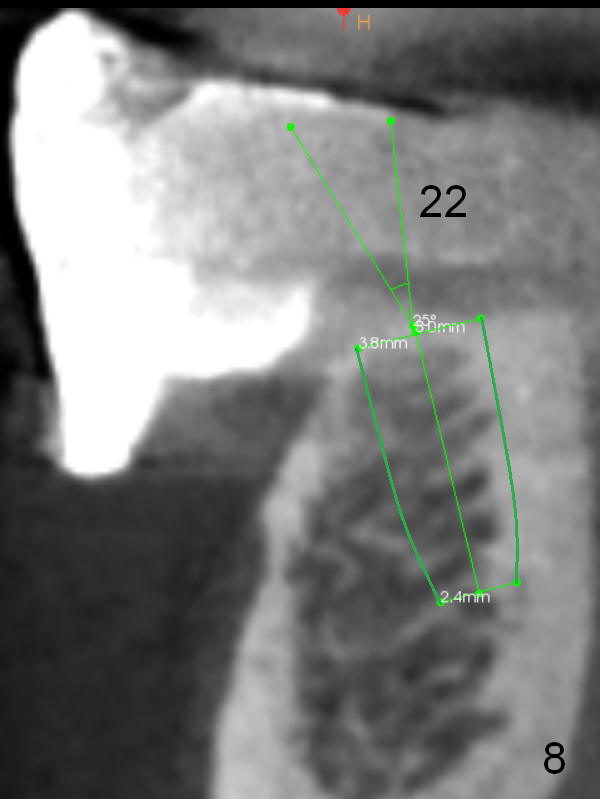

The patient wants to change unstable complete dentures to fixed ones. Because the problem of pain is associated with the lower left (Fig.1 the left Inferior Alveolar Nerve is more superficial), the lower arch will be reconstructed first. Totally 6 implants will be placed for bridges/crowns. Due to time constraint, four implants are placed at the 1st stage (#21, 22, 27 and 28 (Fig.4,5,8,9)); the lower denture will be retained immediately by ball abutments and soft relined. Two to three months later, two more implants will be placed (at #31 and 20, Fig.2,10). Note severe atrophy of the crest at #18 and 19 (Fig.11 and 12). If primary stability is achieved, a fixed immediate provisional will be fabricated.

In contrast to the upper arch, the bone density in the lower arch is high. The challenge is bone height. Short implants will be used (6 mm for #31 (Fig.2) and 8 mm for the majority of the others (at premolar and canine sites). If needed, extra implants will be placed at incisor sites (Fig.6,7 (implant can be longer)) and at #29 (Fig.3) . If a site is too small for a 3.8 mm 2-piece implant, a 1-piece one may be placed.